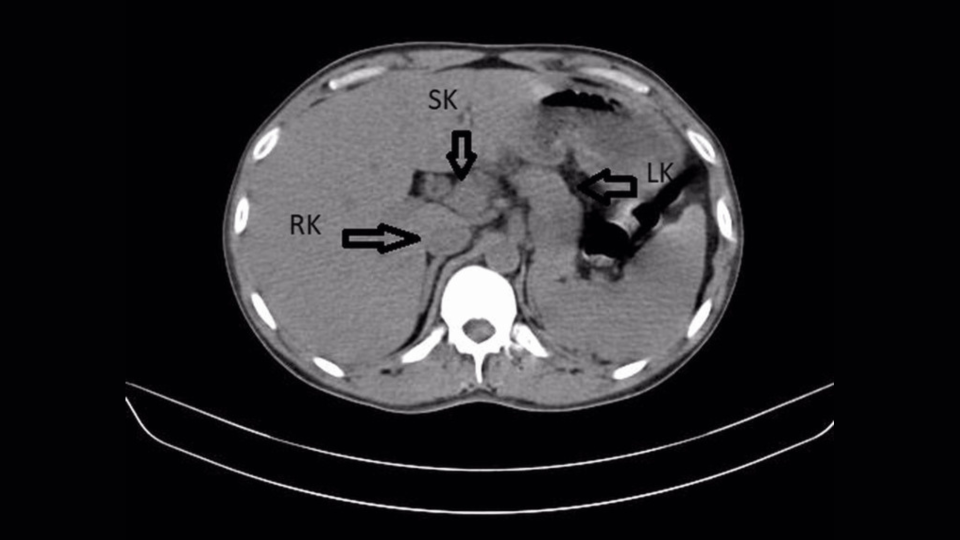

Diagnostic dilemma: A man’s back pain led to the discovery of a third kidney

The patient: A 31-year-old man in Wardha, India

The symptoms: The man visited a medical center after experiencing five days of pain on the right side of his lower back, as well as a burning sensation during urination and a fever higher than 102.2 degrees Fahrenheit (39 degrees Celsius).